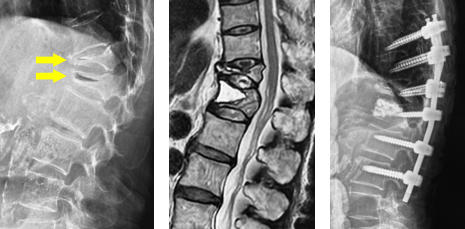

第4腰椎に前屈時に増強するすべりを認め不安定性を示しています。 -

MIS-TLIF(低侵襲腰椎後方椎体間固定術) 椎間板にケージと言われるスペーサーが挿入され、また経皮的に椎弓根スクリューの挿入とロッドの連結がなされ、第4腰椎のすべりが矯正され固定されています。